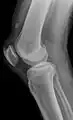

An x-ray demonstrating quadriceps tendon rupture. Note the abnormal angle of the patella and soft-tissue swelling marked by the arrow.

A quadriceps tendon rupture is a tear of the tendon that runs from the quadriceps muscle to the top of the knee cap.[1]